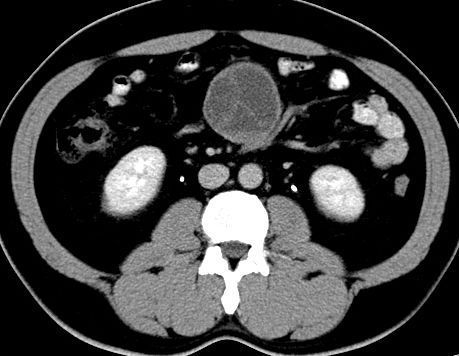

(腹腔)神经鞘瘤

男,48岁,间断性下腹不适1年。

手术探查

:距回盲部28厘米处肠系膜根部可见5*7cm左右包块,质中等硬度,活动度尚可,肝、胆、胰、脾肾未见明显异常。

病理

:(腹腔)

神经鞘瘤

,伴出血、坏死及囊性变,伴淋巴结反应性增生。

免疫组化结果

:sma(-), desmin(-), cd117(-), s-100(+++), nf(-),vimentin(+++).